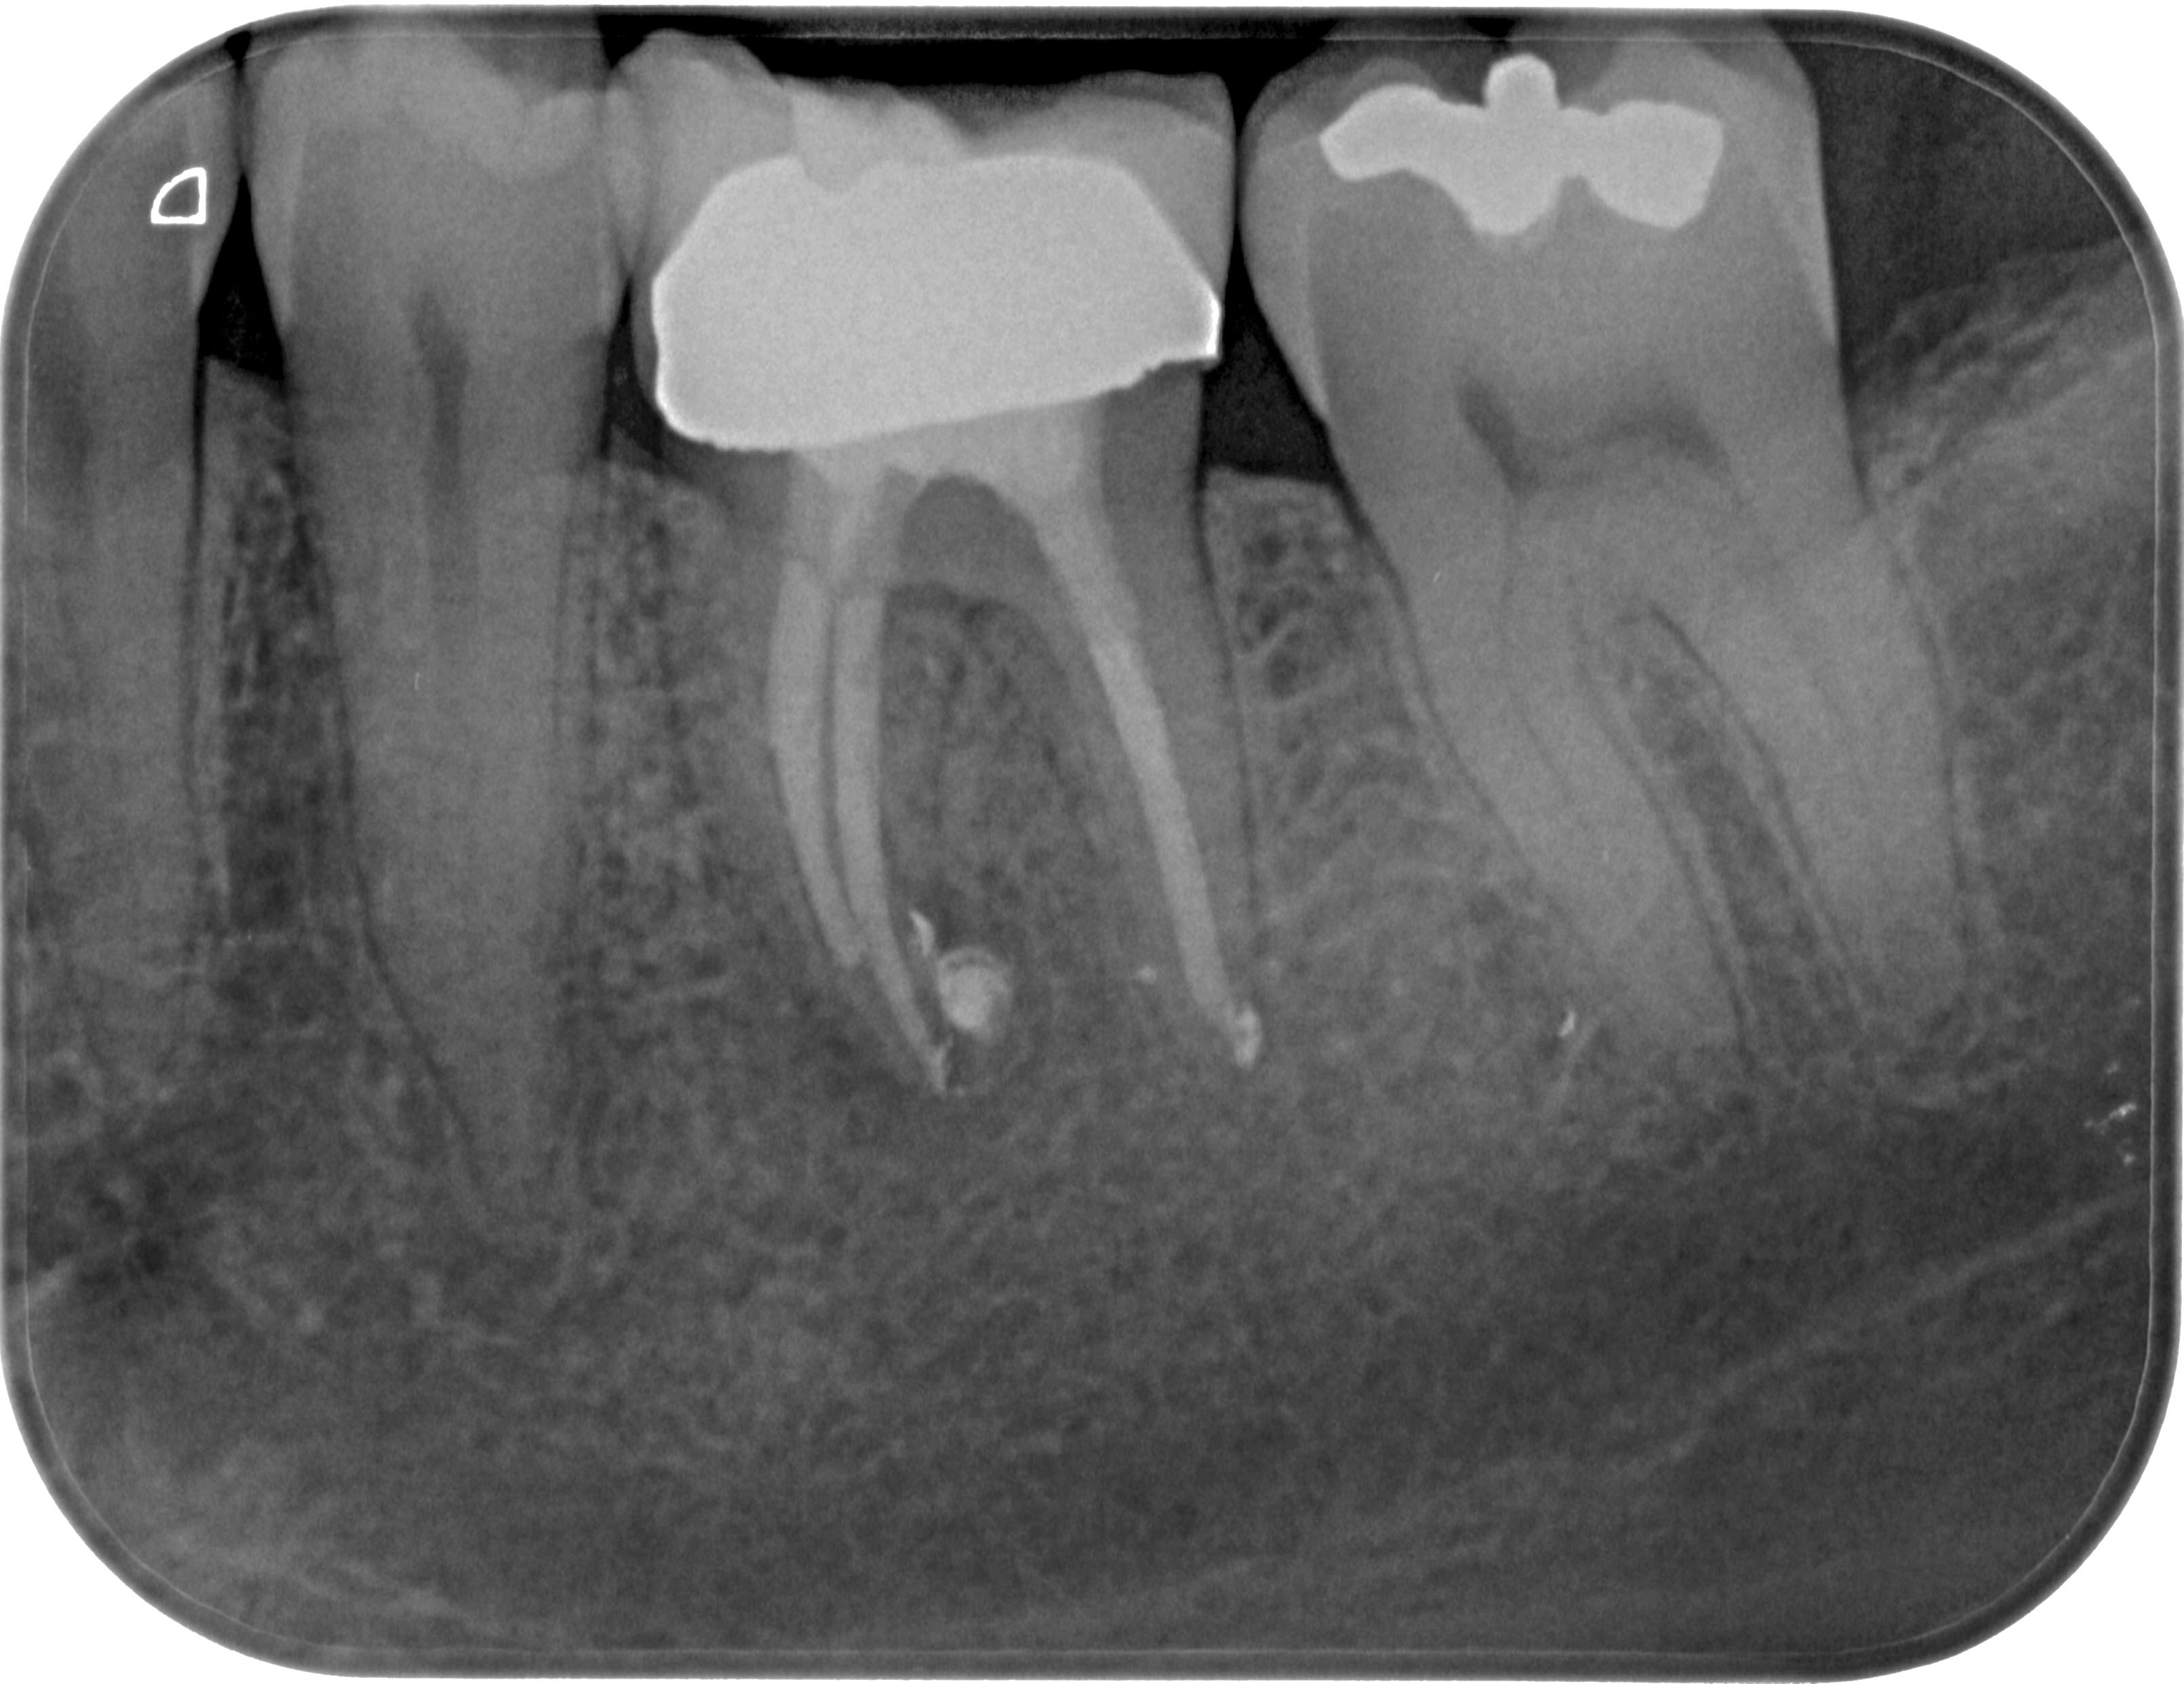

FM36 (5 von 6) Veröffentlicht 21. März 2016 am 3220 × 2483 in Calciumhydroxid- Überpressung (2) 14. Dezember 2012